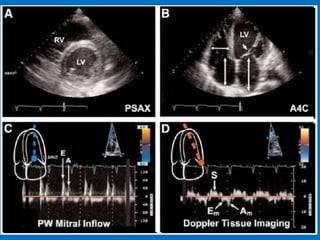

• 2 D - Echo

SEGMENTAL WALL MOTIONABNORMALITIES IN DILATED CARDIOMYOPATHY • Regional wall motion abnormalities observed in at least 50% of patients with non-ischemic causes of dilated cardiomyopathy • Most frequent wall motion abnormalities: – anterior wall & apex • Posterior and lateral walls most likely to be preserved • Type of abnormality: – hypokinesis (83%) – akinesis (11%) – dyskinesis (6%) • Heterogeneity in regional oxidative metabolism using C- 11 acetate clearance has been demonstrated in DCM AJC 1990;65:364-70; Arch Int Med 1992;152:769-72; JACC 1995;25:1258-62